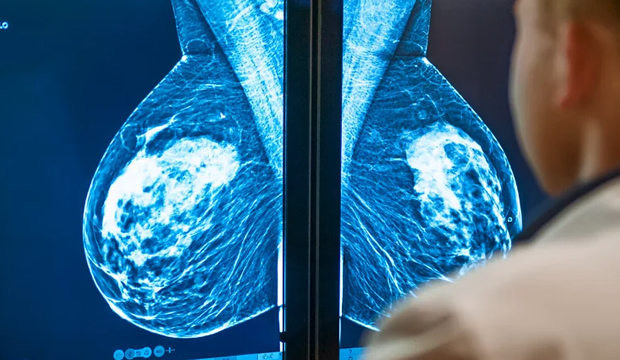

«Una mastografía utiliza rayos X para obtener imágenes del tejido mamario mediante la compresión del seno desde distintos ángulos —de arriba hacia abajo y de lado a lado—», explica la Dra. Kelli Ha, radióloga de mama en el Hospital Houston Methodist. «Nos da una visión general, es como una especie de mapa del tejido mamario». Cada año, tu radiólogo revisa nuevamente ese “mapa” de tus mamas, buscando cambios que puedan señalar la presencia de cáncer.

«La gran mayoría de los cánceres de mama se detectan de esta forma, por eso la mastografía es el estándar de oro», añade la Dra. Ha. «Pero el ultrasonido también puede jugar un papel importante en la detección y el tamizaje del cáncer de mama».